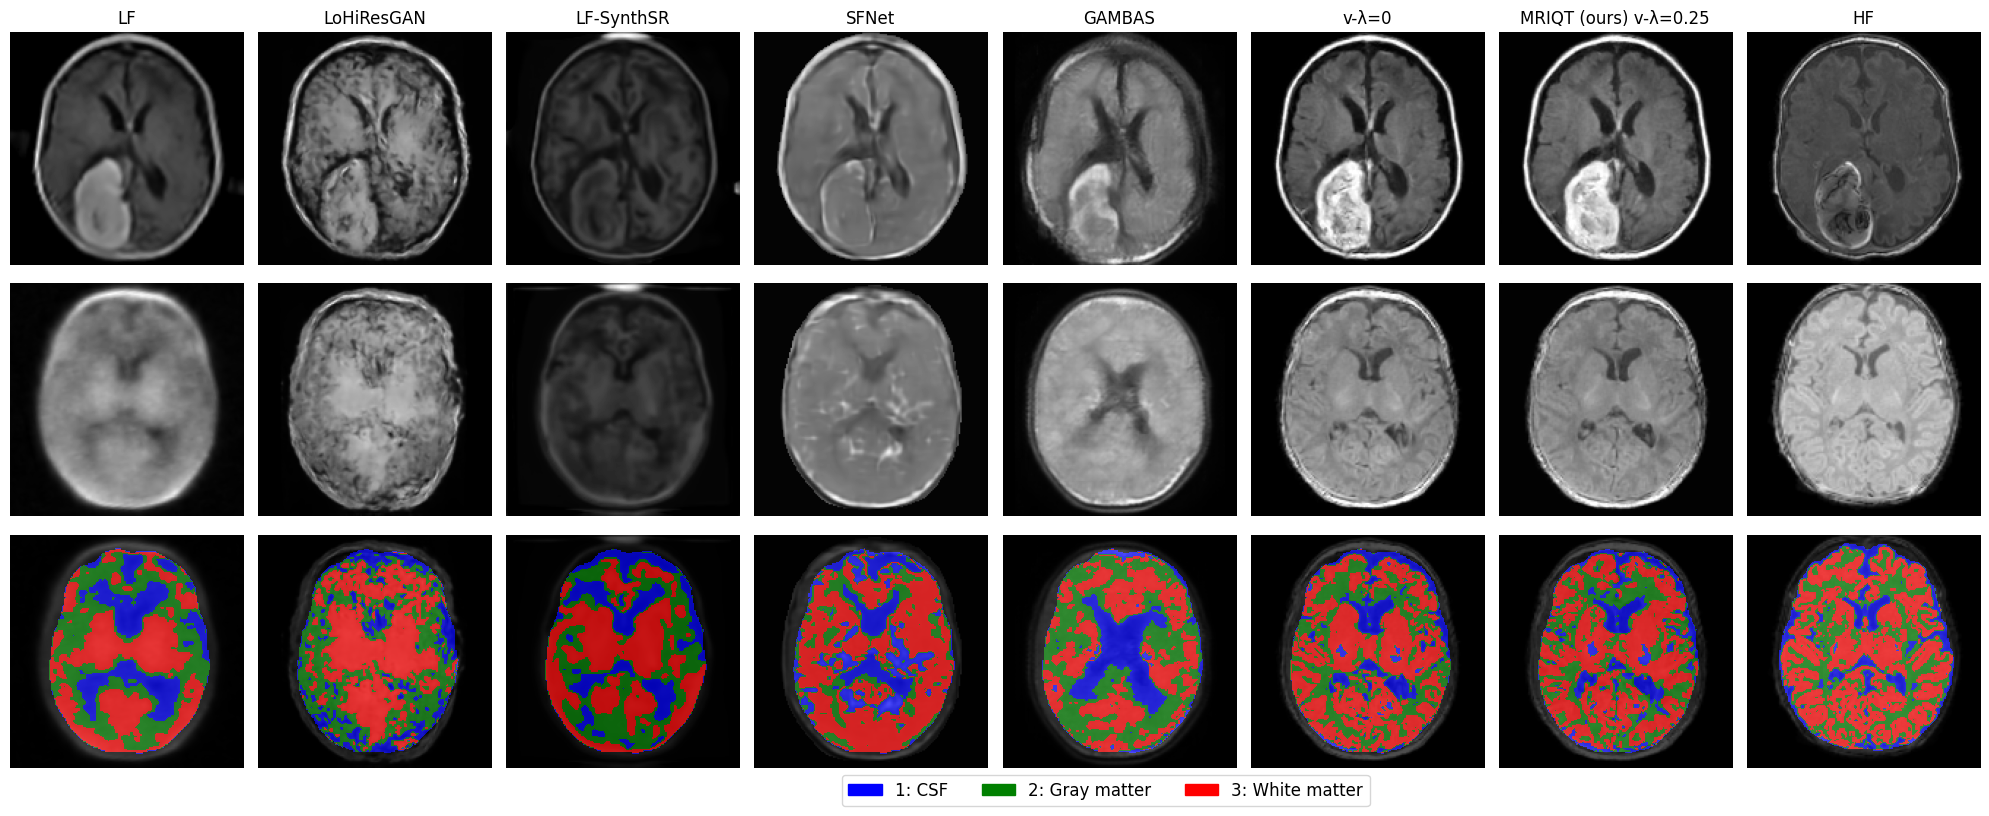

Refer to caption

Fig. 3: Qualitative comparison of 2 samples on the axial view. The first and second rows correspond to the generated samples, while the third row presents the corresponding tissue segmentation results for the second sample. Left to right: ULF, LoHiResGAN [Islam2023improving], LF-SynthSR\ddagger [iglesias2022quantitative], SFNet\dagger [Tap_SuperField_MICCAI2024], GAMBAS\dagger [baljer2025gambas], Our base model, Ours, reference HF. [(\dagger) trained on T2w-scans, (\ddagger) testing requires both T1w and T2w scans.]

Figure 3 compares uLF, SoTA, and MRIQT reconstructions across two representative samples (first 2 rows). Competing GAN-based models (e.g., LoHiResGAN, SFNet) tend to oversharpen or hallucinate fine structures, whereas MRIQT consistently restores cortical boundaries and deep gray matter contrast without introducing artifacts. MRIQT also preserves pathological features such as hemorrhagic lesions and ventricular enlargement, closely aligning with the HF reference. The segmentation results on the second sample (third row) further highlight MRIQT’s superior anatomical consistency, showing clearer tissue separation and reduced misclassification compared to competing methods. Overall, the denoising smoothness and texture recovery confirm that diffusion-based IQT generalizes effectively across unseen pathologies.